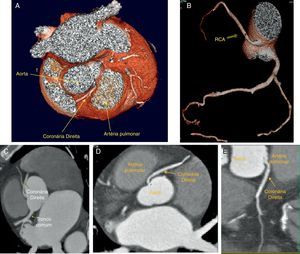

Tomografia computorizada multidetetores; painéis A e B: 3D volume-rendered demonstrando a origem da coronária direita na parede ântero-lateral esquerda da aorta, acima os seios de Valsalva e com trajeto inicial entre a aorta e a porção ascendente da artéria pulmonar; painéis C, D e E: imagens de reconstrução multiplanar demonstrando o trajeto extramural e interarterial da coronária direita.

RCA: coronária direita; Pulmonary ASC: artéria pulmonar; LM: tronco comum.